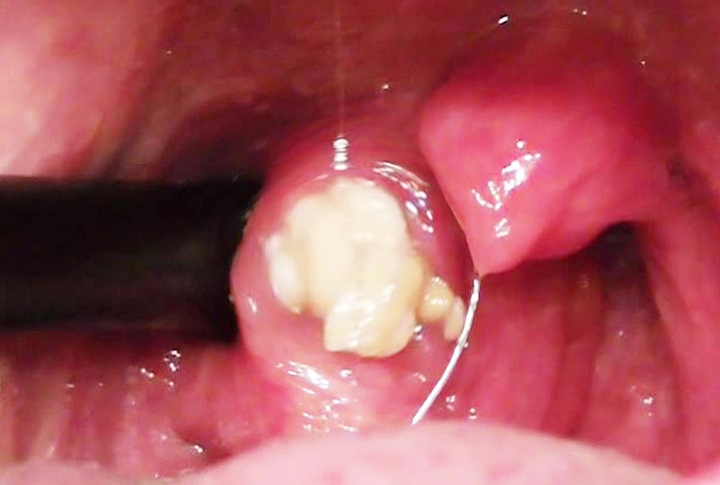

편도결석은 통증과 같은 증상이 없기 때문에 자신이 가지고 있는지도 모릅니다. 편도결석의 크기는 작은 쌀알부터 포도알만큼 크기도 합니다. 만약 양치 후, 가글 후에도 심한 악취가 난다면 편도결석을 의심해 봐야합니다.

편도염, 후비루, 비염 등과 같은 염증이 생긴 이후 그 자리에 구멍이 생겨 점액, 타액, 음식물 찌꺼기가 그곳에 쌓여 생긴 것이 편도결석입니다.

온갖 찌거기가 쌓이다 보니 박테리아, 곰팡이 등이 생겨 악취가 나고 시간이 지나면서 단단해집니다. 사람에 따라 차이가 있지만 하나만 있을 수 있고 여러 개 가지고 있을 수 있습니다.